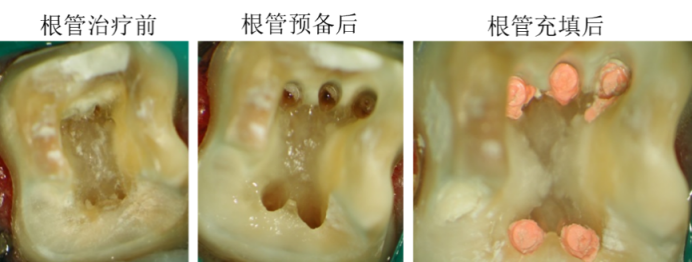

近年来,根管治疗已告别“凭手感、靠经验”的传统模式,进入显微数字化时代。

在显微镜放大20–40倍的视野下,医生可:

·定位肉眼难辨的细小根管、钙化根管

·识别微裂纹及隐藏的感染腔

·实现精准开髓,最大限度保留健康牙体